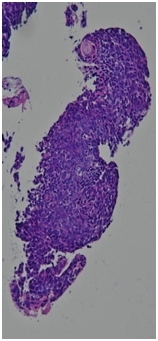

Бронхоскопия 11.01.2017.

Центральный рак правого легкого.

Гистологическое заключение. Высокодифференцированная плоскоклеточная карцинома с ороговением (G1) на всю толщину фрагментов.